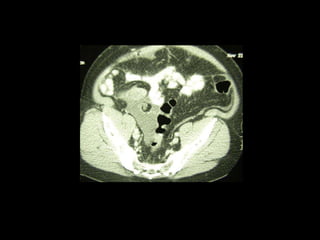

Peritoneal cavity with mucinous tumor in the pelvis

CT

Pseudomyxoma peritpnii

Bowel wall thickening and

fold swelling

Multiple non-enhancing

intraperitoneal masses